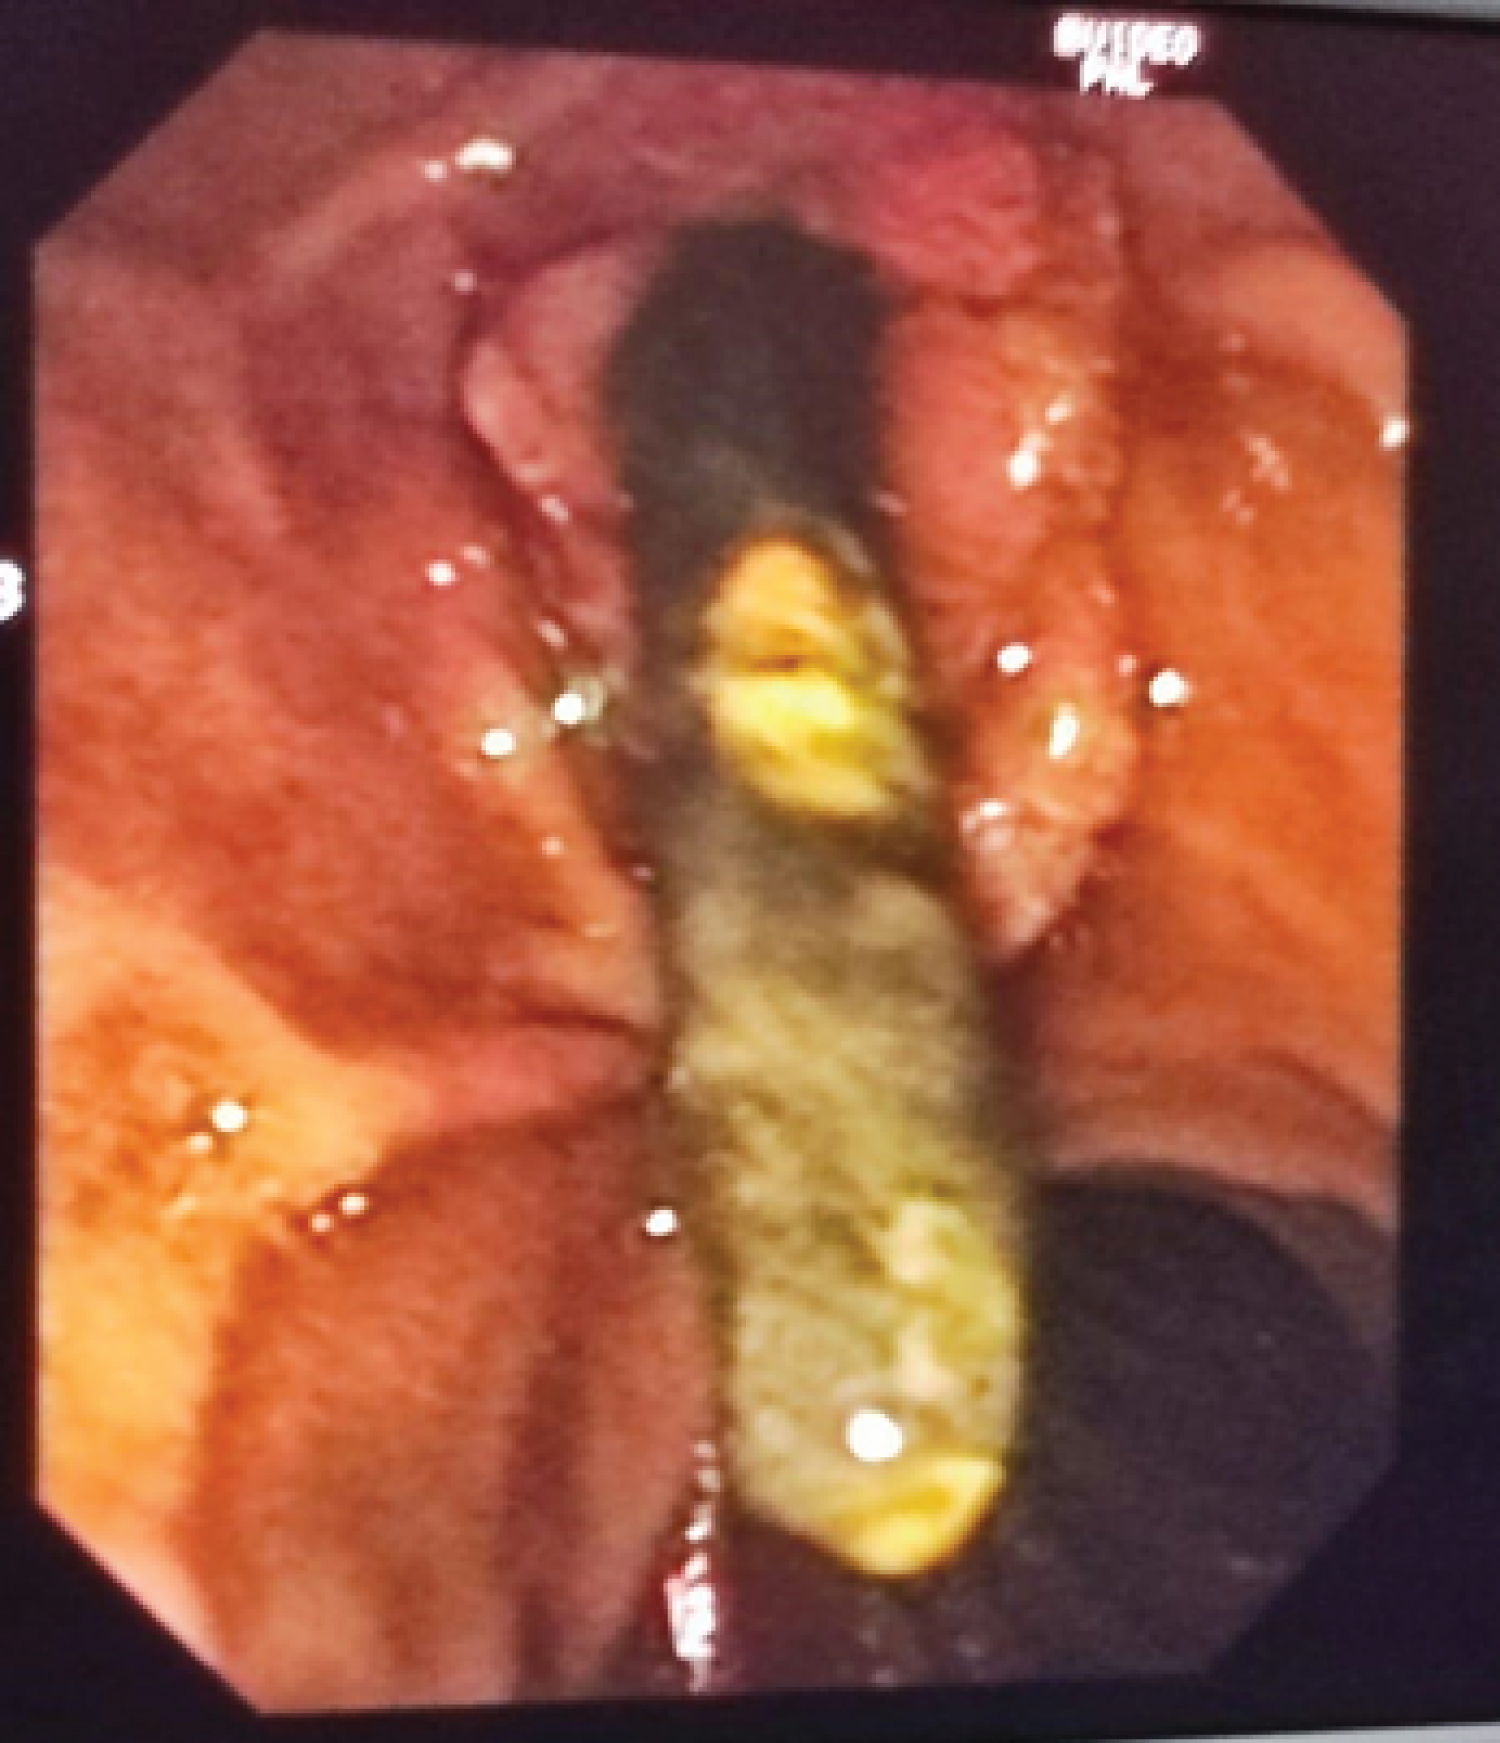

All procedures were performed by experienced endoscopists (> 500 ERCPs) or surgeons (> 50 CBDEs) (Photomicrograph 1, Photomicrograph 2 and Photomicrograph 3).

Photomicrograph 1: Showed the hologram of the endoscopic technique of ERCP to remove the CBD stone. View Photomicrograph 1

Photomicrograph 2: Showed the hologram of the endoscopic technique of ERCP to remove the CBD stone. View Photomicrograph 2